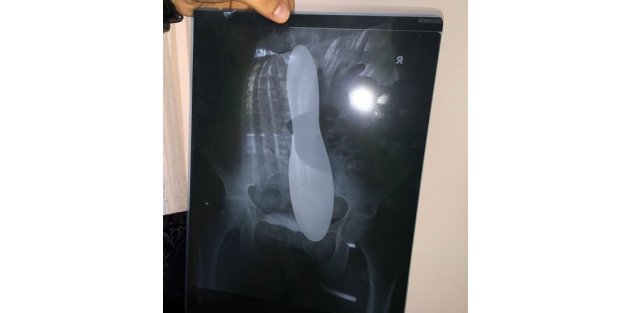

İstanbul’da, karın ağrısıyla kaldırıldığı hastanede dalak ameliyatı olan 35 yaşındaki Fatma Soylu’nun karnında, organları ayırmaya yarayan cerrahi mala unutuldu. Ameliyattan 43 gün sonra şiddetli karın ağrısının gerçek nedenini öğrenen Soylu, farklı bir hastanede karnından çıkartılan yaklaşık 30 santimetre uzunluğundaki malayı görünce bayıldı. Soylu, malayı unutan doktorların kendisinden özür dahi dilemediğini, alelacele yeni bir ameliyat yaparak ‘küçük bir alet unutulmuş, onu çıkaracağız, olumsuz hiçbir şey yok’ dediğini söyledi.

Haseki Hastanesi’nden çıkıp özel bir hastanede ameliyat olan ve karnından çıkarılan 30 santim uzunluğundaki ‘cerrahi ekaratör mala’yı gösteren Soylu, “Bu büyüklükteki bir malayı karnımın neresinde unuttular bilmiyorum. Ama içimden çıkan şey bu. Özür dilemedikleri gibi bunun olabilir bir durum olduğunu söylediler.” dedi. Malayı ilk gördüğünde bayıldığını büyük bir şok yaşadığını belirten talihsiz kadın, doktorunun en az bir sene boyunca korseyle gezmesi gerektiğini, en küçük bir ağırlık kaldıramayacağını ve hiçbir iş yapamayacağını kendisine anlattığını söyledi.